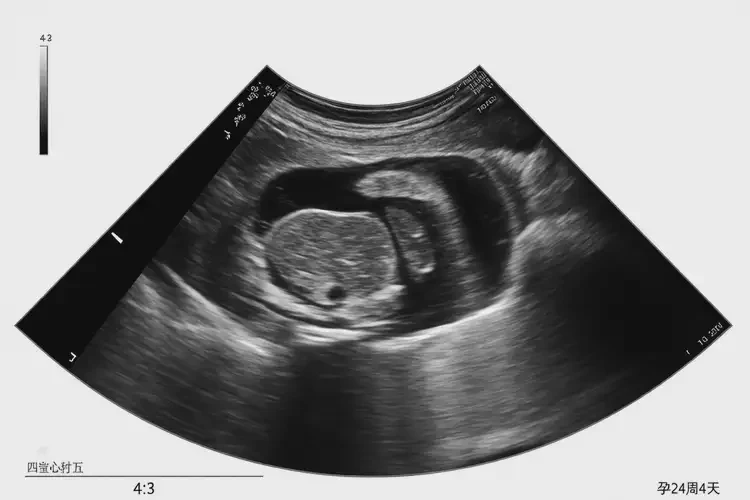

孕24周4天胎心率164寶寶還能要嗎

胎心率164次/分鐘在孕24周4天屬于正常范圍,寶寶可以要。

胎心率是指胎兒心臟每分鐘跳動的次數(shù),是評估胎兒健康狀況的重要指標之一。在孕24周4天,胎兒的胎心率正常范圍通常在140-170次/分鐘之間。胎心率為164次/分鐘的胎兒是處于正常范圍內(nèi)的,無需過于擔心,寶寶是可以要的。

孕24周4天胎心率164寶寶還能要嗎(圖1)

3. 超聲檢查:通過超聲檢查可以觀察胎兒心臟的結構和功能,評估胎心率是否正常。